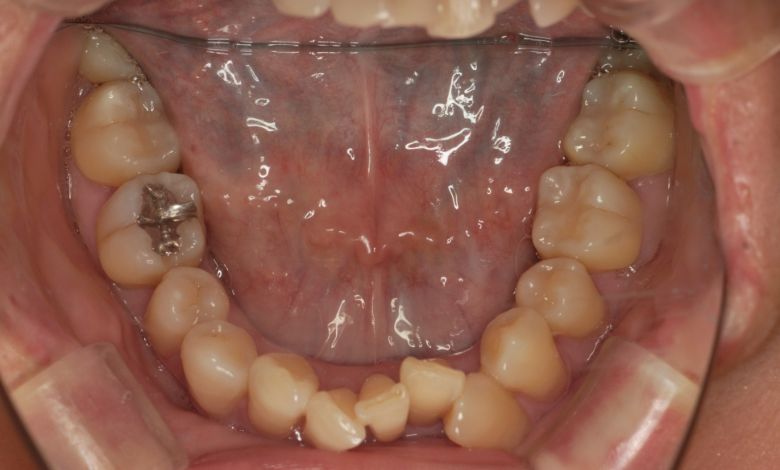

他院にて上下左右4本の抜歯を前提とした矯正治療を提案されていました。上顎・下顎ともに歯列弓が狭く、

V字型の弓状を呈していたため、叢生(歯の重なり)が強く、噛み合わせにも不調和が見られる状態でした。

上顎歯列はV字型に近く、全体的にアーチが狭窄している状態

叢生が解消され、歯列全体にわたり滑らかで調和のとれた配列が得られています

精密検査の結果、抜歯を行わずに歯列弓を拡大する治療方針を選択。歯が正しい位置に並ぶスペースを

確保したことで、歯列は自然なU字型に整い、叢生が解消されました。見た目の改善だけでなく、

咀嚼機能の向上や清掃性の改善といった機能面での効果も期待できます。